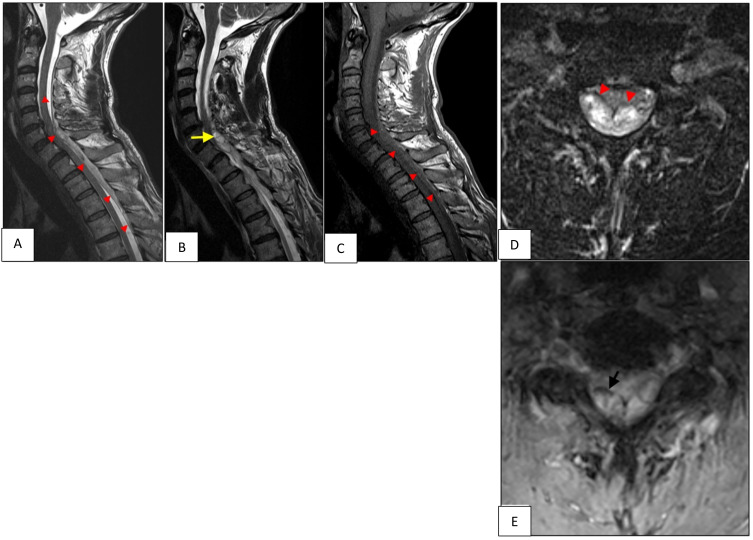

自发性脊髓硬膜外血肿(SSEH)是一种罕见的病理,对患者有潜在的严重后果。由于其罕见的发病率和频繁的非典型表现,SSEH很容易被误诊。抗凝或抗血小板治疗与SSEH之间的关系已在多个病例报告和文献综述中得到描述。我们报告一例61岁男性患者,接受抗凝和抗血小板治疗(分别为利伐沙班和氯吡格雷),诊断为脊柱SSEH,经椎板切除术和血肿清除后恢复良好。然而,SSEH的治疗指南很难找到,并且没有明确的抗凝和抗血小板治疗管理策略。本报告的目的是强调在选定病例中快速诊断和手术治疗的重要性,并对这些患者的抗凝和抗血小板管理及其预后提供见解。

Spontaneous spinal epidural hematoma (SSEH) is a rare pathology with potentially severe consequences for the patient. Given its uncommon incidence and frequent atypical presentation, SSEH can easily be misdiagnosed. The association between anticoagulation or antiplatelet therapy and SSEH has been described in multiple case reports and literature reviews. We present a case of a 61-year-old man on anticoagulation and antiplatelet therapy (Rivaroxaban and Clopidogrel respectively), diagnosed with spinal SSEH with good recovery after laminectomy and hematoma evacuation. However, treatment guidelines for SSEH are difficult to find and there is no clear strategy about management of anticoagulation and antiplatelet therapy. The aim of this report is to highlight the importance of rapid diagnosis and surgical therapy in selected cases and to give an insight on the anticoagulation and antiplatelet management in these patients and their prognosis.